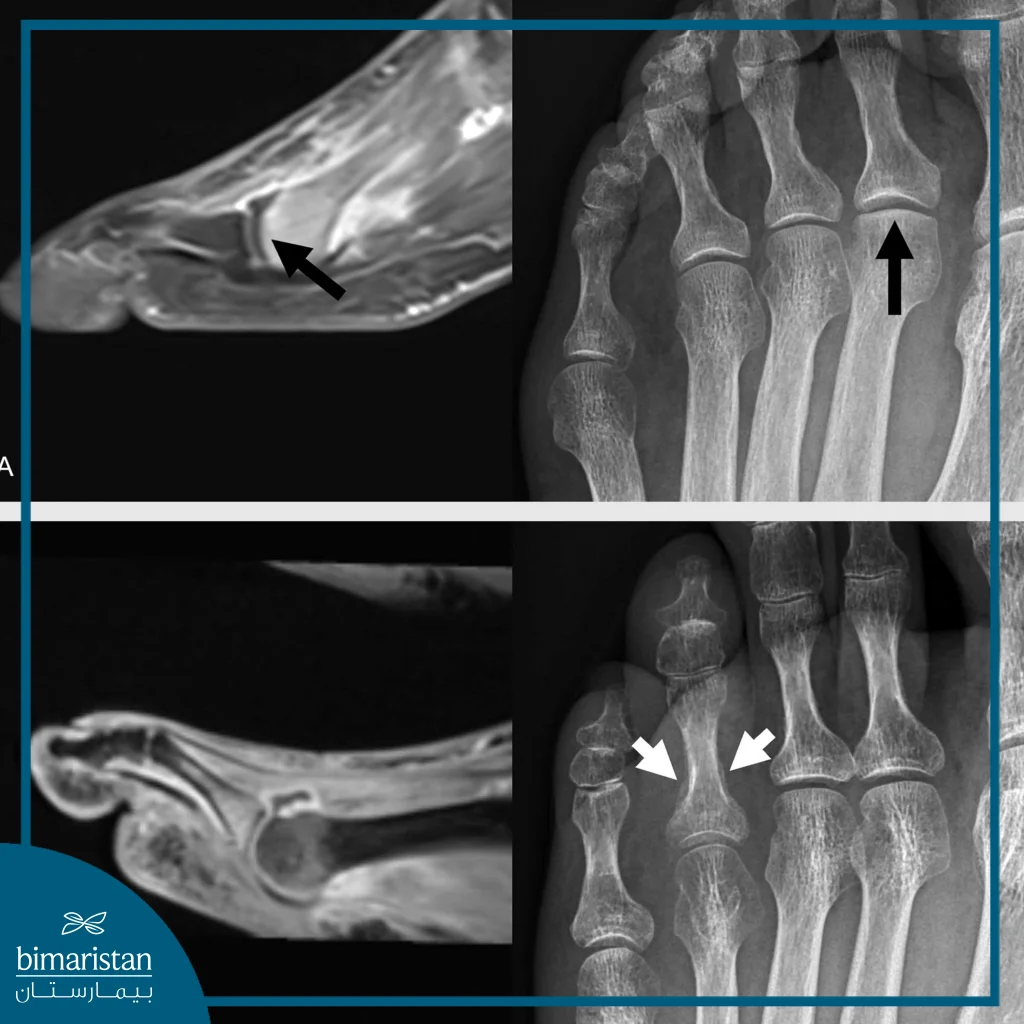

التصوير بالرنين المغناطيسي

يُستخدم لتقييم الأنسجة الرخوة المحيطة بالعظم مثل الأربطة والأوتار والغضاريف، كما يُعد وسيلة فعّالة لاكتشاف كسور الإجهاد التي قد لا تظهر في الأشعة السينية المبكرة، يُلجأ إلى الرنين المغناطيسي عندما يكون الألم مستمراً رغم عدم ظهور كسر واضح في الأشعة التقليدية أو عند الاشتباه بوجود تلف في المفصل أو الأربطة.

التصوير المقطعي المحوسب

يُستخدم هذا الفحص عندما تكون الأشعة السينية غير كافية لإظهار تفاصيل العظم بدقة خصوصاً في حالات الكسور المعقّدة مثل كسور الكعب أو المفصل تحت الكاحل. يوفّر التصوير المقطعي صوراً ثلاثية الأبعاد تسمح للطبيب بتقييم مدى تفتت العظم ومحاذاة القطع العظمية، يُعتبر أداة مهمة قبل التخطيط للجراحة أو عند الحاجة لتقييم دقيق لمضاعفات ما بعد الكسر.